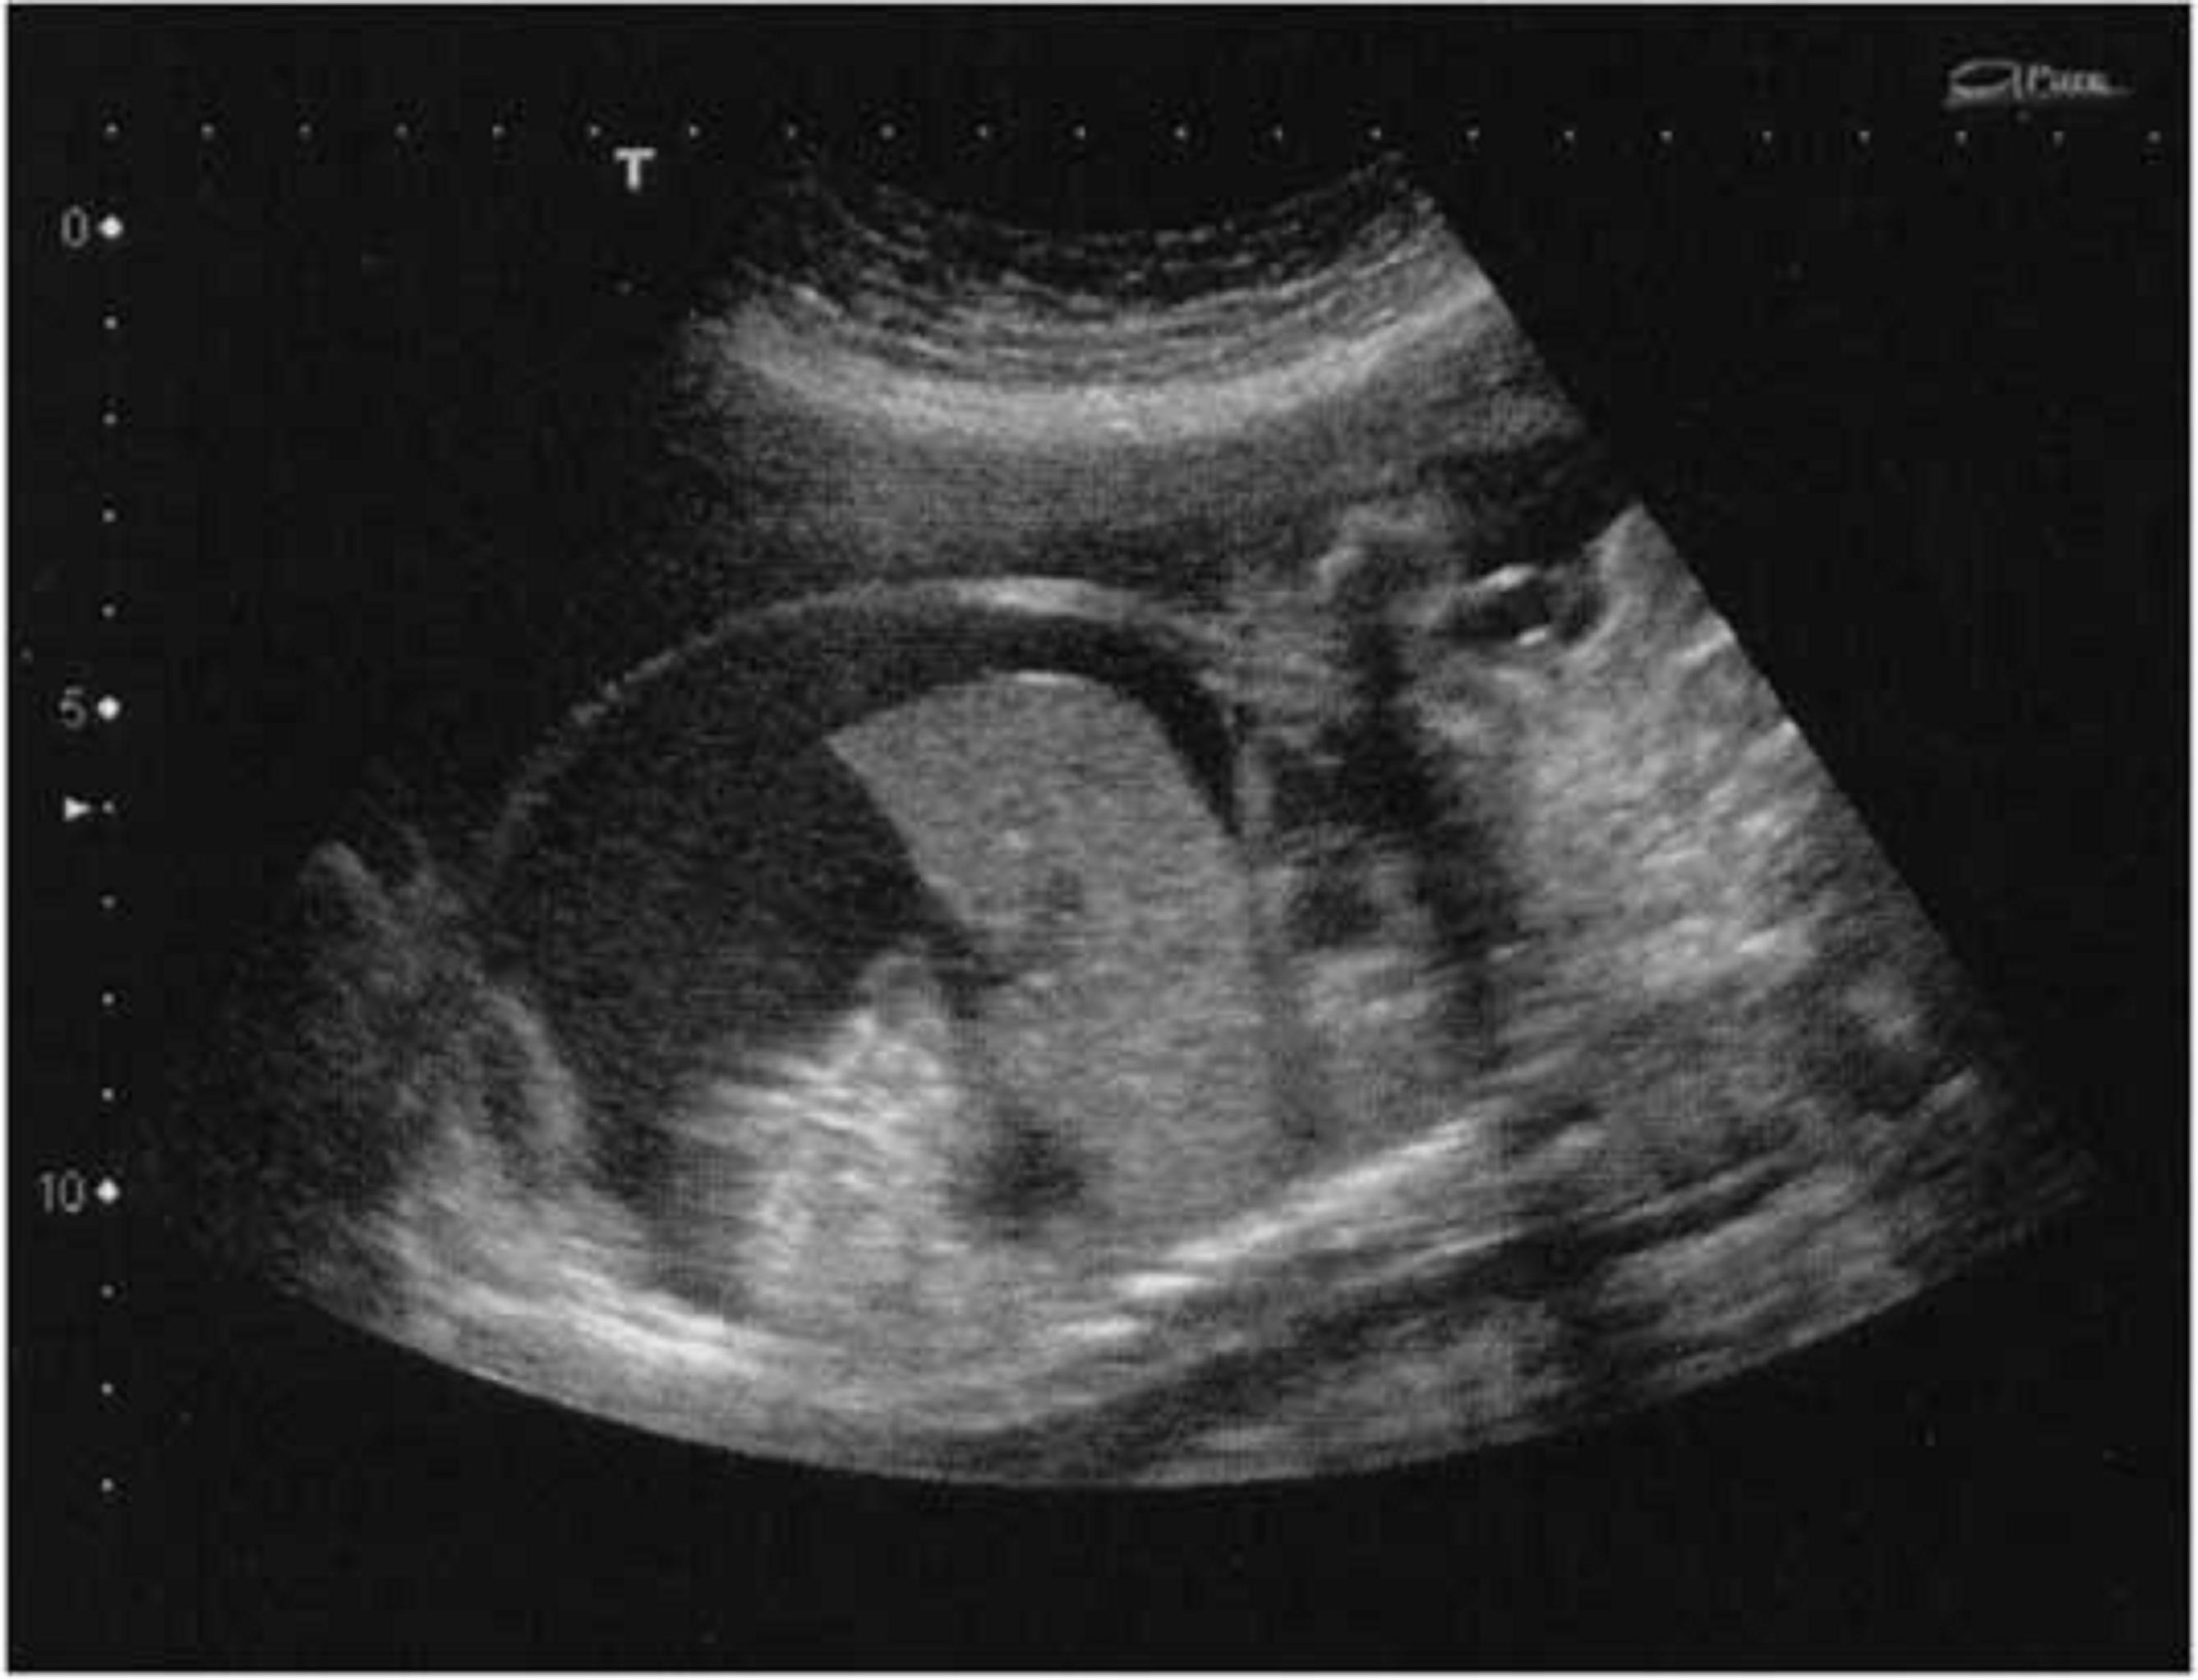

Au-dessus de ce seuil de 5 UI/mL, une surveillance par échographie DopplerDéfinitionExamen échographique en deux dimensions non-invasif qui permet d'explorer les flux sanguins intracardiaques et intravasculaires. Elle est basée sur un phénomène physique des ultrasons, l'effet Doppler. hebdomadaire (voir doppler) doit être réalisée à la recherche de signes d'anasarque fœtale (figure 1) et d'une accélération du flux artériel cérébral fœtal. L'enregistrement du rythme cardiaque fœtal peut aussi permettre d'identifier un tracé sinusoïdal, caractéristique de l'anémie fœtale (figure 2).

Figure 1 : Anasarque fœtale généralisée

Anasarque fœtale généralisée. L'ascite est ici au premier plan.